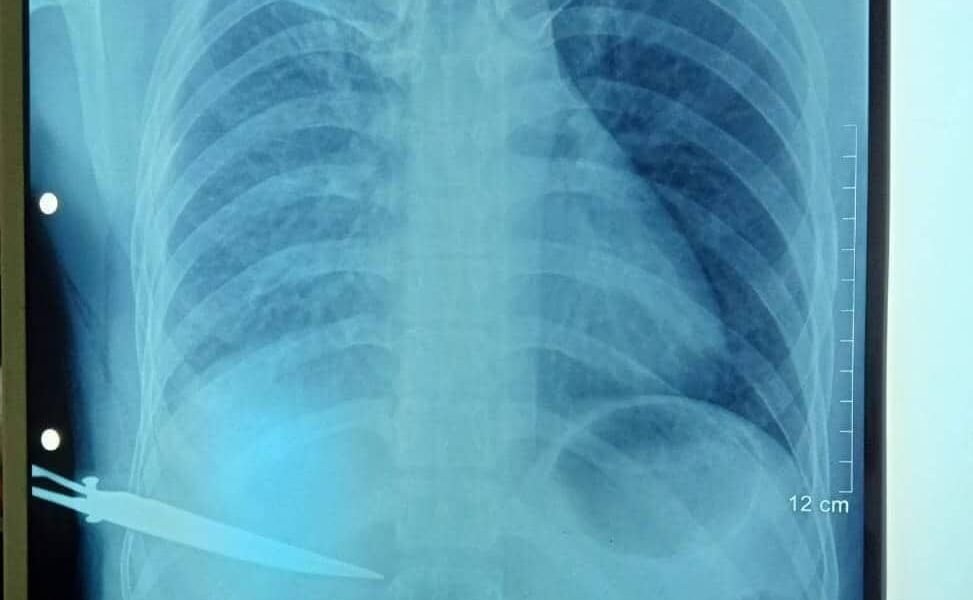

Hatutan.com, (09 Janeiru 2023), Díli—Kazu insidente sona kanek vítima iha área Bidau, besik Ponte BJ Habibie iha Sábadu (07/01/2023), to’o oras-ne’e seidauk bele fó ninia deklarasaun...